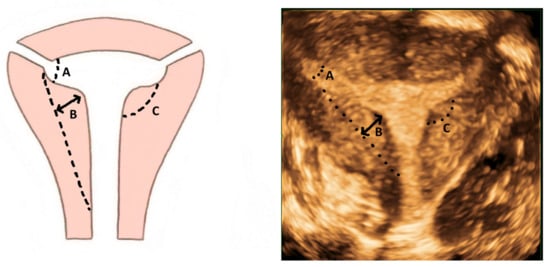

While the T-shaped uterine cavity is diagnosed subjectively by some authors, the ESHRE/ESGE has suggested diagnosis based on a narrow uterine cavity due to thickened lateral walls without specifying a definition and cut-off for thickened lateral walls and narrow uterine cavity [21]. The CUME group proposed a lateral indentation angle ≤ 130°, lateral indentation depth ≥ 7 mm and T-angle ≤ 40° as the criteria for diagnosing a T-shaped uterus (Figure 10) [22].

Figure 10. Criteria for diagnosing T-shaped uterus according to CUME ([22]). A—T-angle ≤ 40°; B—lateral indentation depth ≥ 7 mm; C—lateral indentation angle ≤ 130°.